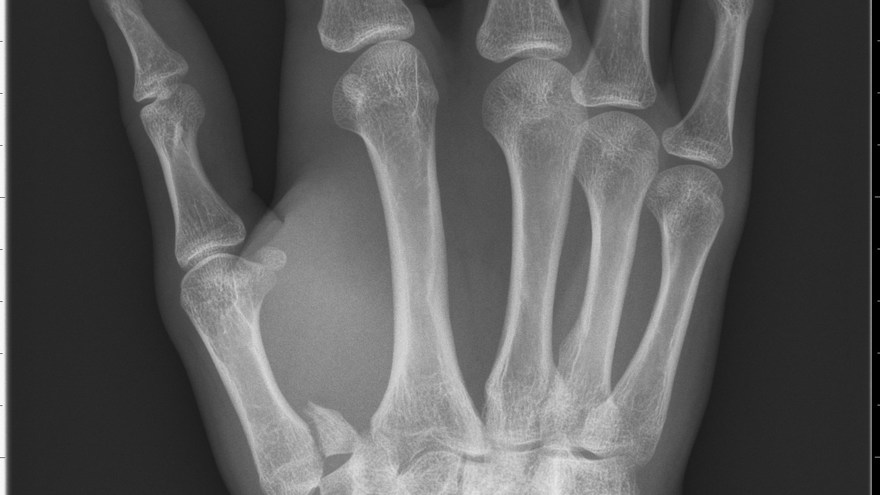

Bennetfraktur

Bennetfraktur är en intraartikulär luxationsfraktur genom basen av metacarpale I. Metacarpalbasen tenderar att luxera genom APL senans dragning i radiell-proxmal riktning. Frakturen behöver därför i princip alltid reponeras och immobiliseras internt med stift. Kan se väldig beskedlig ut på primära bilder men dislocerar succesivt genom senans dragning – klassificeras därför som ”lurig”.

Mekanism vid Bennetfraktur

Bennetfraktur där det ulnara fragmentet i basen på metkarpalen hålls kvar med hjälp av ligament i karpus. På grund av drag i abductor pollicis longus (APL) uppstår nästan alltid en diastas i frakturen. Diastasen i ledytan ger sekundärt artros. Dessa frakturer kräver således exakt fixation – vanligen i form av stift eller skruv.